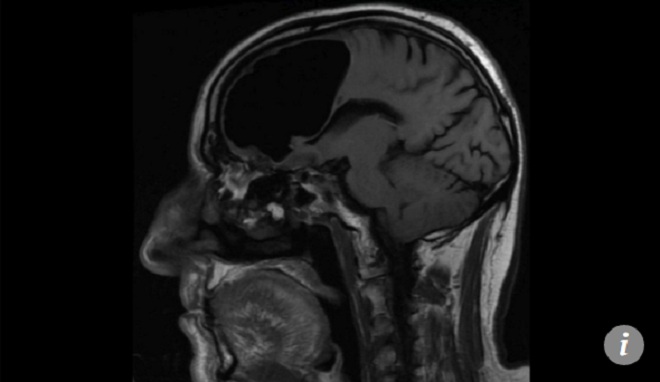

Khoảng trống khổng lồ bên trong não bệnh nhân.

Nói cách khác, các bác sĩ không nhận thấy điều gì bất thường, cho đến khi đưa bệnh nhân đi chụp CT và MRI. Đó là lúc các bác sĩ cảm thấy kinh ngạc khi trong đầu bệnh nhân có một khoảng trống lớn, dường như là do bóng khí hình thành. Khu vực này lẽ ra là nơi chứa thùy não phải của bệnh nhân.

Khoảng trồng thực chất là bong bóng khí chèn ép thùy não phải.

Bệnh nhân chưa từng trải qua bất kỳ một ca phẫu thuật não nào. Khoảng trống lớn trong đầu bệnh nhân dài tới 8,9cm, chứa toàn không khí.

Bệnh nhân dường như bị một khối u trong não, tạo thành van một chiều hấp thụ không khí từ bên ngoài. Quá trình này diễn ra tới hàng năm, mỗi khi ho hay hắt hơi, bệnh nhân vô tình đưa một lượng không khí nhất định vào phần não.